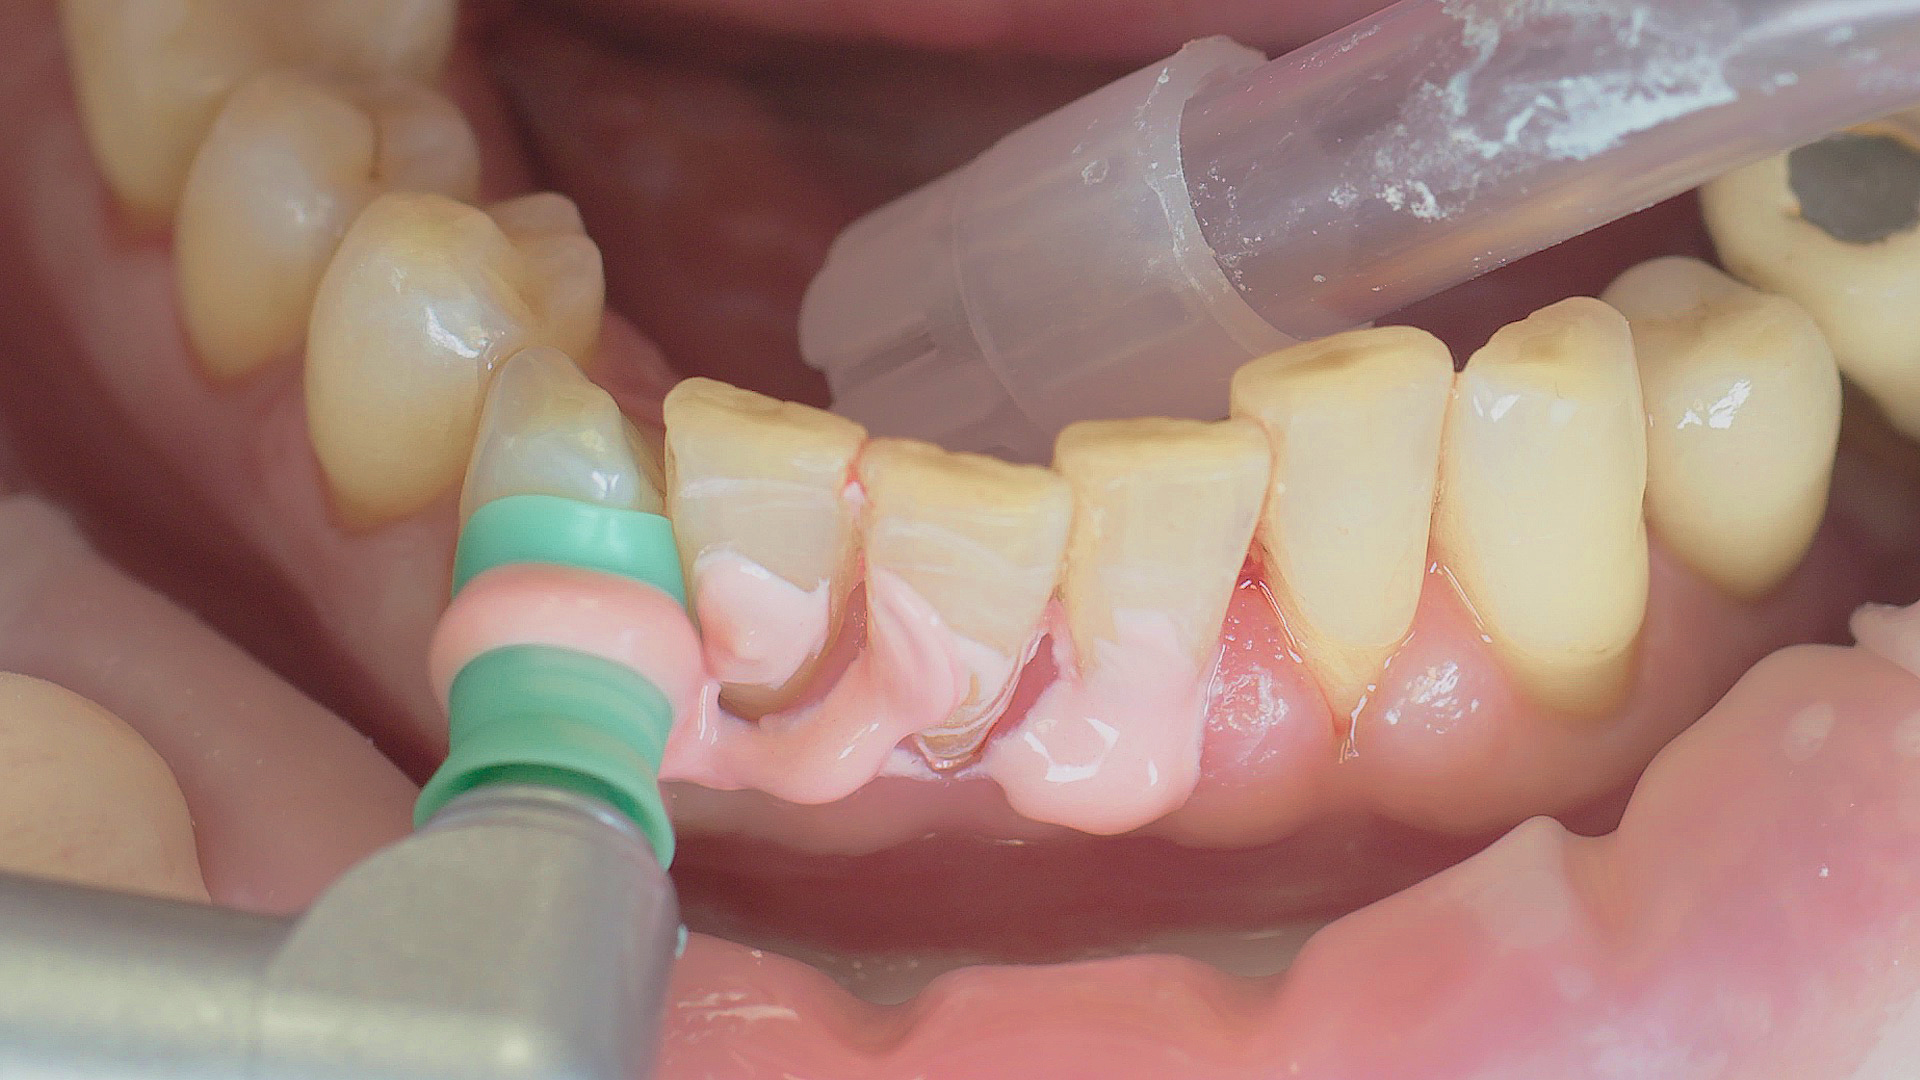

Un détartreur à air réalise un détartrage initial efficace, une étape du traitement parodontal initial.

Fig. 2 : Un détartreur à air réalise un détartrage initial efficace, une étape du traitement parodontal initial.